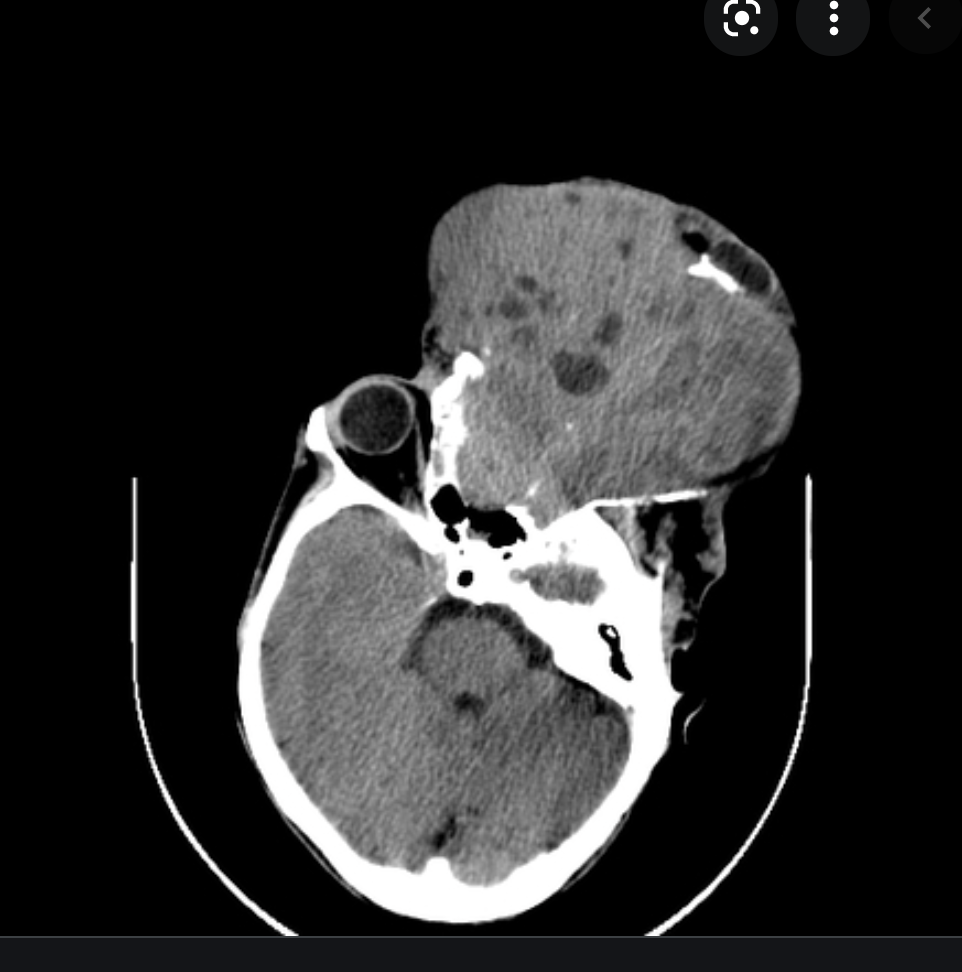

Central skull base Basal cephalocele